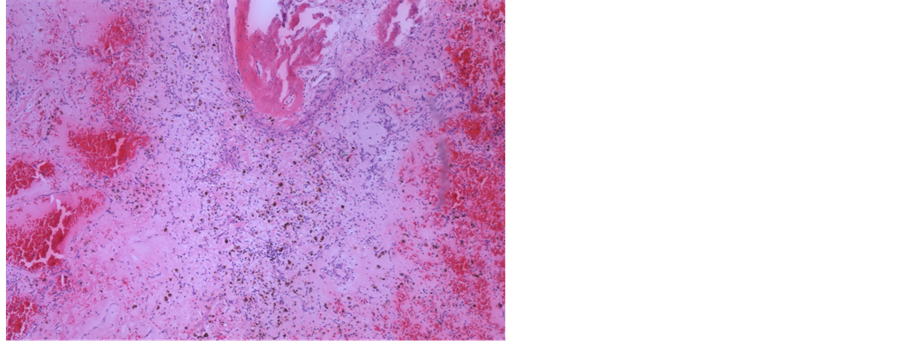

The patient underwent surgical treatment with a median sternotomy, and during surgery a tumour the size of a golf ball was removed (Figure 4). Histologically, it proved to be myxoma (Figure 5). The patient had an uneventful postoperative course and was discharged 5 days after the surgery in well-being. Echocardiography performed four months after the surgery showed no evidence of myxoma recurrence and the patient was asymptomatic, without adverse events.

Figure 5. Left: photograph shows the macroscopic resected left atrial mass, sliced before histology. Right: the classic structure of cardiac myxoma is shown. There are areas with larger vessels containing blood (left), fresh bleeding (right) and calcification with suggested osseous metaplasia (top centre). (H & E, orig. ×10).